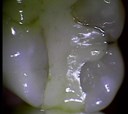

É um exame realizado através da captura de imagens, por uma câmera intraoral de alta definição, que permite analisar com precisão a saúde de cada dente. Desta forma, pode-se detectar o início de uma cárie, antes mesmo de ela ser visível a olho nu, por exemplo.

• check up preventivo digital - imagem de tartaro antes do tratamento  (fonte: Catálogo interno)

• check up preventivo digital - imagem logo após a remoção do tártaro.